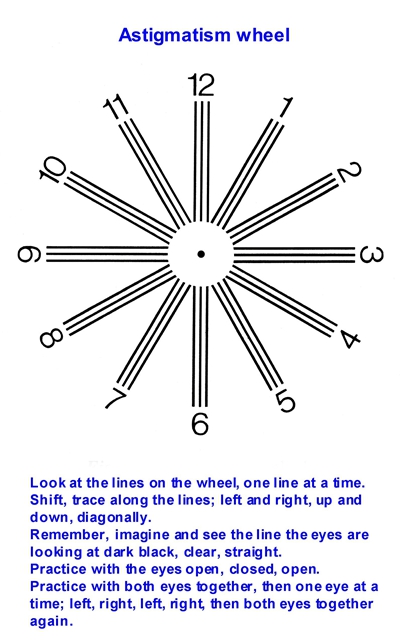

A:判斷自己有沒有散光,最簡單的方法是使用散光表來測試。散光表是一種簡單、方便的方法,但是它的準確度不是特別精確。在配鏡的情況下一般再用裂隙法,或者是交叉圓柱鏡法來精調散光的度數。散光表在網上可以看到,它類似於鐘錶的盤面,有12個數字。各個鏡線……